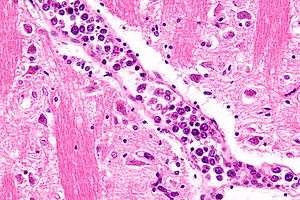

| Micrograph showing an intravascular large B-cell lymphoma in a blood vessel of the brain. H&E stain. | |

The diagnosis is established by the examination of tissue under the microscope (i.e. biopsy or autopsy) and immunohistochemical stains. Intravascular lymphomas have a large cell morphology, i.e. the malignant cells are two or more times the size of a normal lymphocyte, and typically have a prominent nucleolus.

Most intravascular lymphomas are of the B-cell lineage.[4][9] Most cases of intravascular lymphoma are caused by the infiltration of B-cells into the lumens of small blood vessels.[6]